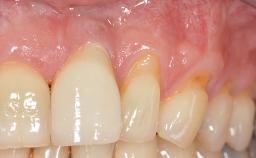

Adequate peri-implant soft-tissue thickness is essential not only for esthetic but also for functional reasons. In this case, Vincenzo Iorio Siciliano demonstrates how he achieved increased height and thickness of posterior peri-implant soft tissues to obtain a stable mucosal seal and a width of keratinized tissue favorable to toothbrushing.

The patient, a healthy 38-year-old woman, was referred for increasing the width of the keratinized tissues at the buccal aspect of dental implant 46. The site exhibited a premature-closure screw exposure caused by trauma during chewing, with inadequate keratinized tissue.